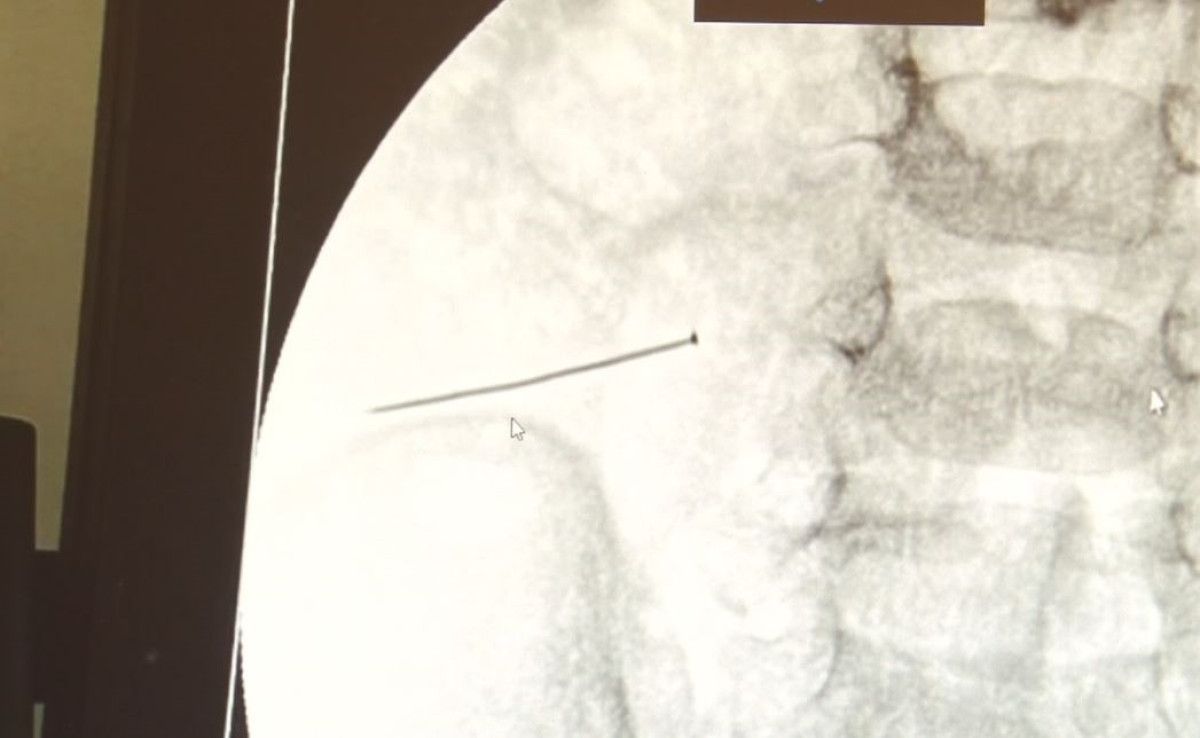

Burada yapılan tetkiklerde 2 yaşındaki çocuğun ince bağırsağında yaklaşık 3 santimlik toplu iğne olduğu ve bağırsağı deldiği belirlendi.

Ertesi gün bağırsakta delinmeyle sonuçlanmış ve çocukta da ciddi semptomlar meydana getirmişti. Bu şekilde hasta bize başvurdu. Tetkikler sonucunda yabancı cismi tespit ettik, semptomları ve bulgularına göre de çocuğu ameliyata aldık. Yaklaşık 3 santim boyunda bir toplu iğnenin ince bağırsağı deldiğini, ince bağırsaktaki içeriğin de karın içerisine dolduğunu gördük. Ameliyatı başarılı bir şekilde tamamladık, yaklaşık 1 saat süren bir ameliyattı” dedi.

Öte yandan, yaklaşık 3 santimlik toplu iğne filme yansıyan görüntüsüyle gözler önüne serildi.